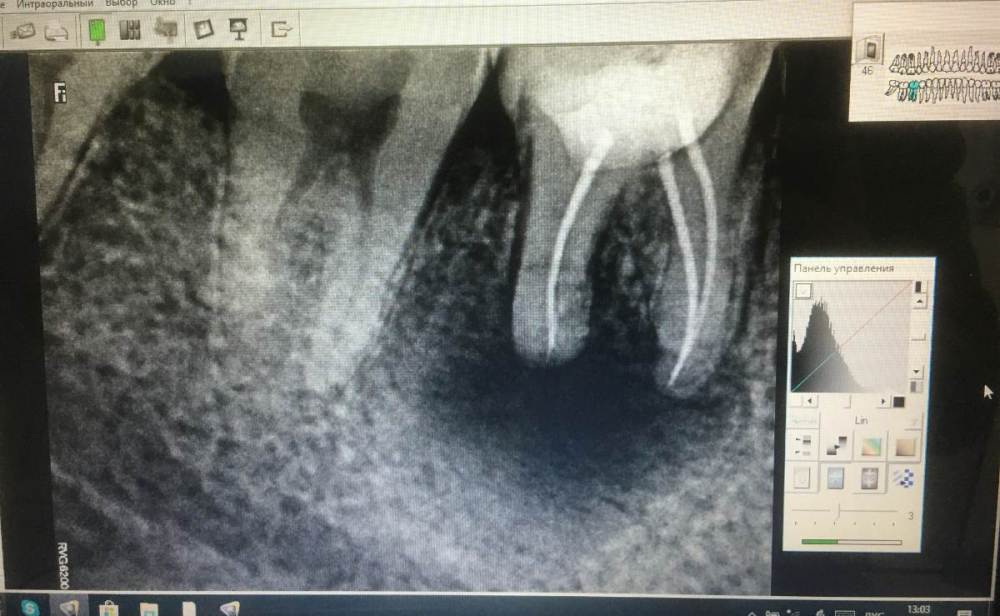

Недавно была гранулема, гной вывели не до конца, сейчас еще во рту небольшой свищ. Как сказал врач по снимку - черное пятно это уже отсутствие костной ткани и срочный вариант решения проблемы - это удаление зуба, полное удаление инфекции, наращивание кости и после протез. Хотел бы узнать - это так? Единственный ли это вариант, возможно ли, к примеру, просверлить насквозь зуб, вывести все, нарастить кость, поставить штифт при необходимости, тем самым сохранив зуб? Или бесполезно?

На 99,9% зуб нужно удалять, но если Вы хотите получить самый точный прогноз - обратитесь к стоматологу-терапевту хорошо владеющему операционным микроскопом и пусть доктор проведёт ревизию зуба, если возьмётся

Что делать дальше тут скажет компьютерная томография через 8-10 недель